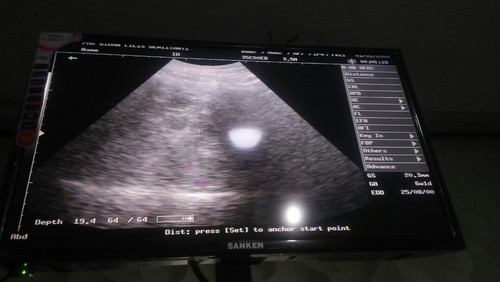

Bun mau tanya kmren saya usg usia 6w nah itu ada bundar 2,apakah kembar ya bun? Kata bidan itu kembar tp agak samar, lalu untuk usia 8w d suruh usg lagi untuk memastikan kembar nya, menurut bunda bagaimana? Trims bun ?

Kemungkinan besar ia bun